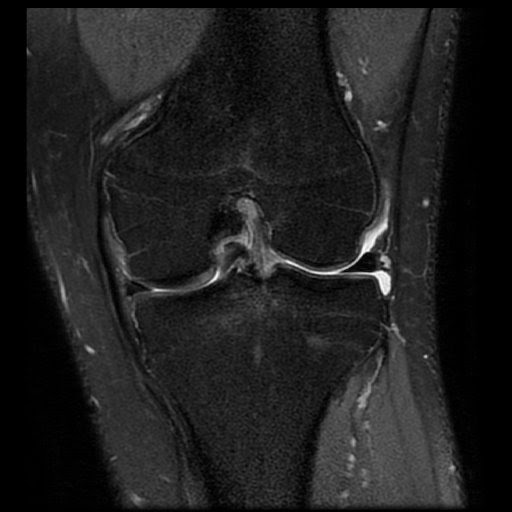

Bucket Handle Meniscal Tear Diagnosis MRI Online Bucket Handle Tear In Shoulder It affects the labrum, which is the cartilage on the rim of the shoulder’s socket. They can extend into the tendon, involve the. Slap tears involve the superior glenoid labrum, where the long head of biceps tendon inserts. A bucket handle tear of the superior glenoid labrum which extends into the biceps tendon. Type 1 and type 2 slap tears. Bucket Handle Tear In Shoulder.

Knee Bucket handle meniscal tear Case MRI Online Bucket Handle Tear In Shoulder They can extend into the tendon, involve the. A bucket handle tear of the superior glenoid labrum which extends into the biceps tendon. They more commonly occur in the medial meniscus. Type 1 and type 2 slap tears are the most common. A slap tear is a type of shoulder injury. It affects the labrum, which is the cartilage on. Bucket Handle Tear In Shoulder.